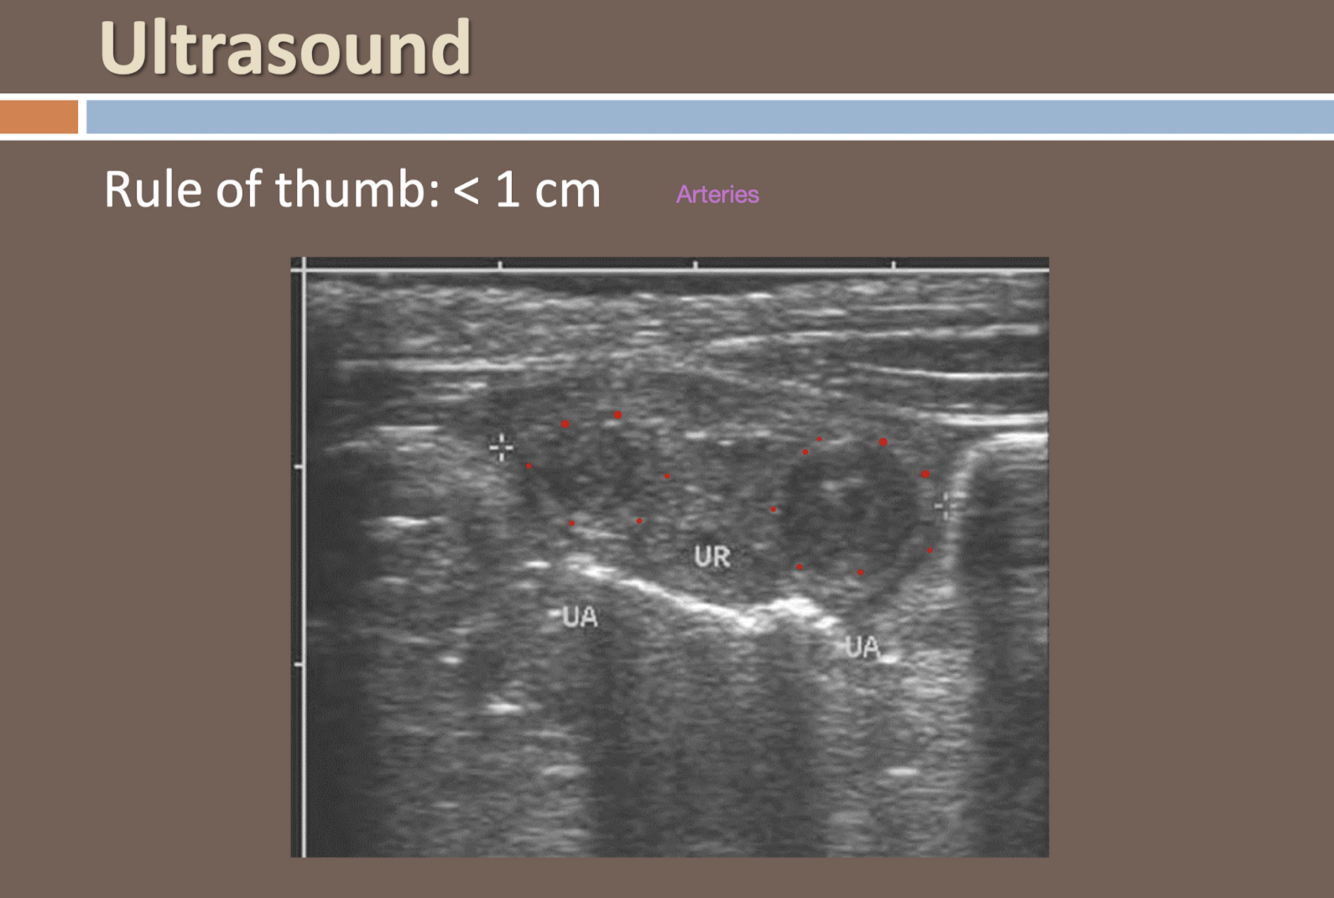

Ultrasound

<1 cm vessel diameter